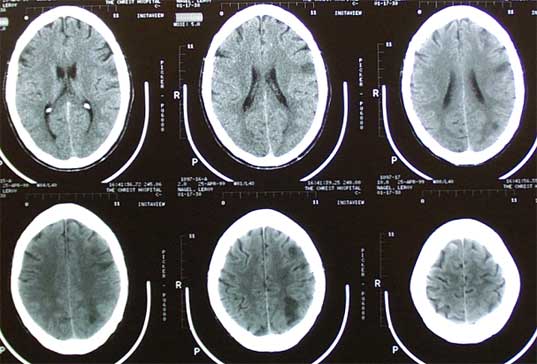

Still, rabies can, under certain conditions, approximate some of the conditions of the zombie lust for brains. The rabies virus causes massive inflammation, or swelling, of the brain, and it's most often transmitted by bites from infected animals. About 55,000 people die annually from rabies, with almost all of these deaths occurring in Asia and Africa. Although vaccines do exist (indeed, it was Louis Pasteur's successful treatment of a rabies-infected child that brought us into the modern age of vaccinations), they have to be administered before the onset of symptoms if the patient is to survive.